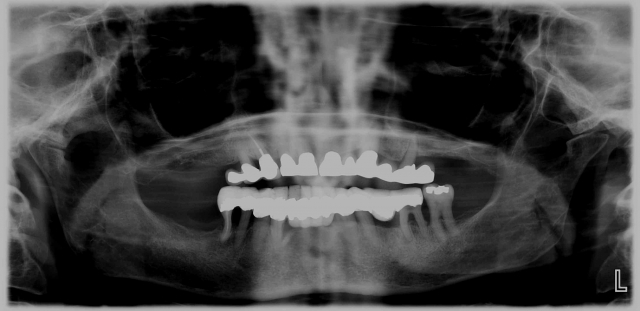

Many of our immediate fixed hybrid patients begin as emergency patients seeking relief from pain. Some begin as new patients unaware of their dental condition. Many patients are unaware of their true dental condition. Photography is the primary way to communicate this reality in an efficient and effective manner. Once we’ve taken the photos and examined radiographs, we can better assess their overall condition. Having the photos for the patient to see is the game-changer. Like the old adage states: “A picture is worth a thousand words.” Once the photos are there, you now have an effective platform upon which you can discuss findings that may warrant a more comprehensive examination.

Photography is the linchpin of the entire co-discovery process. We take six pictures in every new case. Spear teaches that these are the six images that will improve case acceptance. Here’s an example:

If you are not yet taking 35 mm photography of your patients, this is a great time to start. Photographs will not only prove invaluable to you as a clinician but will also affect your patient’s perception of their own oral condition very quickly. The effect can be miraculous. Many times a patient will say to me, “Are those my teeth?”

Rampant root caries, extreme worn dentition and the corrosive effects of GERD are all effectively demonstrated with these photos. These photos get the ball rolling on patients requiring more comprehensive treatments due to a terminal dentition.